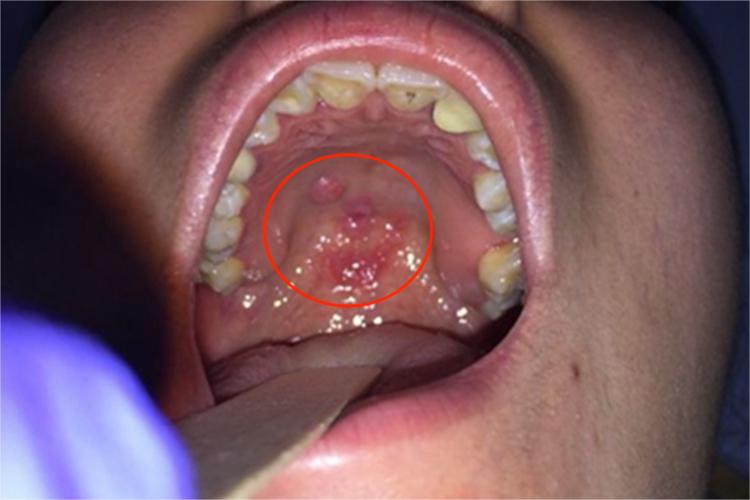

二期口腔梅毒患者口腔黏膜充血,有弥漫性潮红,可出现梅毒黏膜斑,是二期梅毒最常见的口腔损害。损害呈灰白色、光亮而微隆的斑块,圆形或椭圆形,直径约1cm,边界清楚。易发生浅表溃疡,表面覆盖灰白色假膜,周围有红晕。